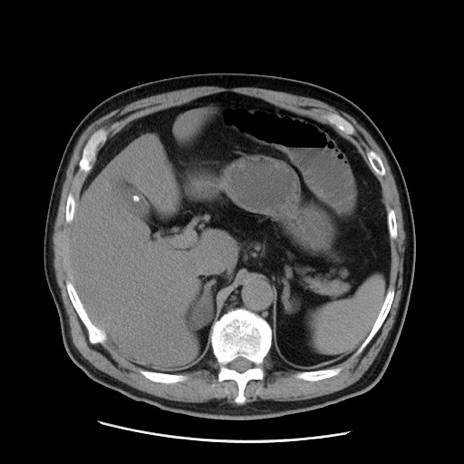

症例20(横断像)

【症例】 60歳代男性

【主訴】 腹部膨満、嘔吐

【現病歴】5日前頃より倦怠感を認め食事量減少し4日前の朝嘔吐、食事摂取困難となった。 3日前近医受診し点滴施行され整腸剤などを処方された。 当日他院を受診し、腹部膨満著明、炎症反応の上昇(CRP10.8、WBC11200)あり、紹介受診となる。

【身体所見】 意識JCS1 受け答えがはっきりしないBP 111/57mHg、 P 67bpm、、BT35.2°C、SpO2 97%(RA)、 腹部:膨隆、打診で鼓音あり、全体的に圧痛有り、腸蠕動音(-)、反跳痛ははっきりせず。

【データ】WBC 11400、CRP 14.20